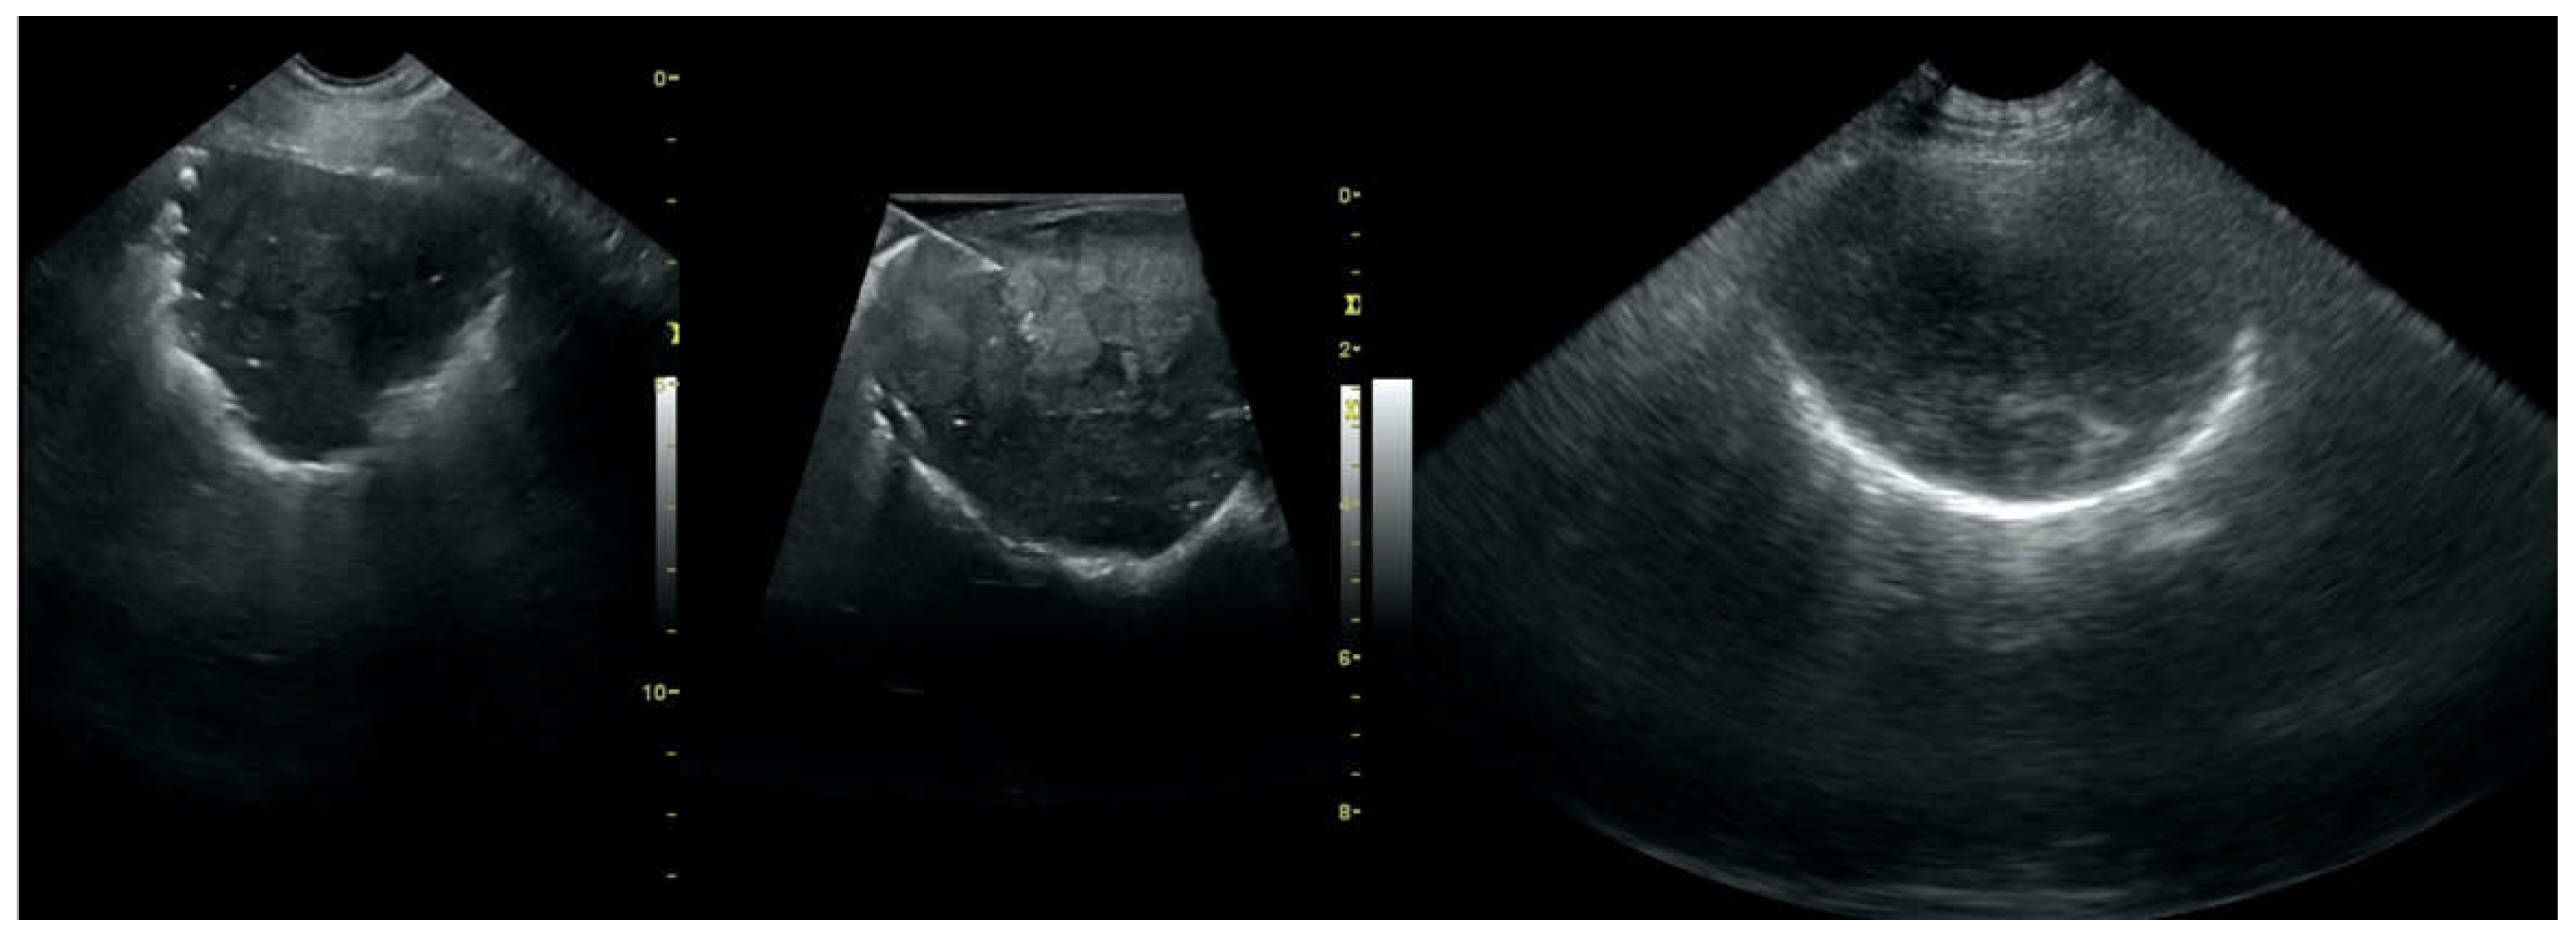

• Pulmonary nodules (≤3 cm in diameter), visualized as an anechoic or hypoechogenic area adjacent to the pleural line of round or oval shape, often with visible B-lines extending from its lower edge (Figure 8), and pulmonary masses (>3 cm in diameter), usually appearing as hypoechogenic masses with a clear-cut deep margin (Figure 9). Pulmonary nodules and masses were merged into one category, henceforth referred to as tumor;

Figure 8. Nodule sign in the course of lung cancer.

Animals 12 01154 g008

Figure 9. Subpleural mass in the course of lung cancer. At the middle scan, biopsy needle is visible.

Animals 12 01154 g009